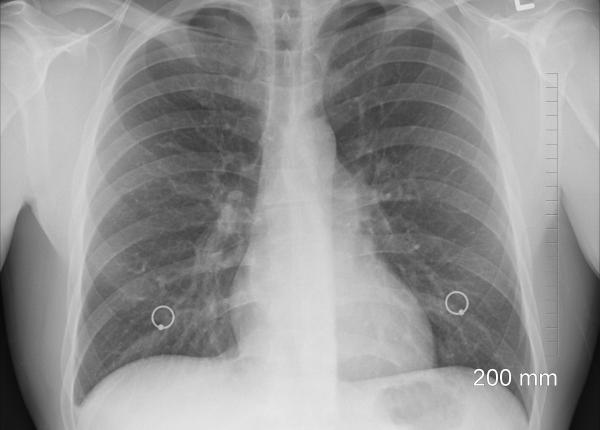

Screening pentru tuberculoză, program uriaș la nivel național. Caravane pentru zonele defavorizate